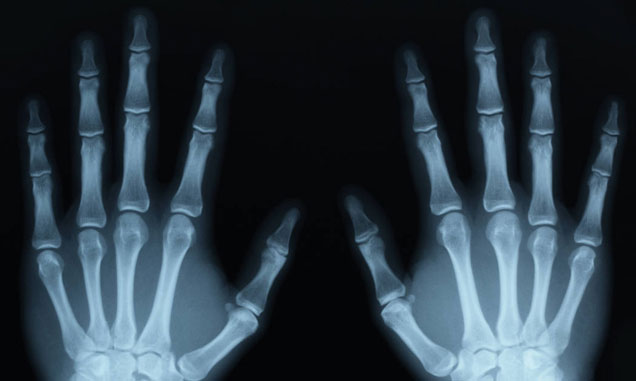

Rentgenoloji müayinə

Rentgenoloji müayinə bəzi məqamlarda çox vacibdir. Bu səbəbdən biz yalnız professional rentgenoloqlarla əməkdaşlıq edirik. El barmaqları üzərində aparılacaq əməliyyat öncəsi müayinə.